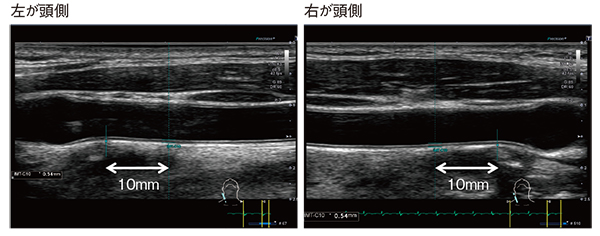

2017年に,「超音波による頸動脈病変の標準的評価法」1)が改定され,内中膜厚(IMT)の計測部位として,IMT-C10とmean IMTの2つが示された。IMT-C10は新しい計測法であり,頸動脈洞より10mm近位側の遠位壁で計測する。また,mean IMTは従来からの計測部位であるが,計測方法が若干変更となり,10mm長の領域で複数点計測した平均値を出す。

Aplio iシリーズでは,IMTが明瞭に描出されるほか,IMT-C10の計測ポイントと計測結果が自動で表示される。さらに,IMT-C10モードは左右どちらにも基準設定が可能なため,患者の頭側が右でも左でも対応することができる(図1)。また,mean IMTの計測法にはトレース法と数点のマニュアル計測があり,現在,ガイドラインではトレース法を基本とする方向性が示されているが,Aplio iシリーズでは,計測法の変化に速やかに対応できる点も魅力である。

図1 Aplio iシリーズによるIMT-C10の計測

IMT-C10モードは頭側が左右どちらでも基準設定が可能